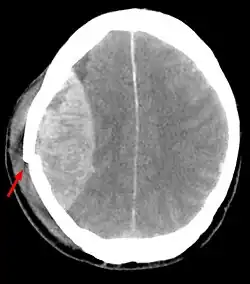

Epiduralhämatom

Ein Epiduralhämatom oder epidurales Hämatom entsteht aufgrund einer intrakraniellen Blutung in den Epiduralraum zwischen Schädelknochen und Dura mater, ausgelöst durch ein Trauma, meist mit Fraktur der Schädeldecke, und verursacht eine Kompression des Gehirns.

Zwei Formen mit prognostisch unterschiedlicher Disposition werden unterschieden:

Beim arteriellen Epiduralhämatom reißen die innen auf dem Schädelknochen liegenden arteriellen Gefäße, insbesondere die Arteria meningea media. Typischerweise folgt ein symptomarmes oder symptomfreies Intervall (Latenz), welches schon Victor von Bruns 1854[5] bekannt war,[6] aber auch komplett fehlen kann, für Minuten bis Stunden. Die Blutung schreitet fort und drückt zunehmend die harte Hirnhaut (Dura mater) und das Gehirn nach innen. Übelkeit, Erbrechen, Bewusstlosigkeit und Pupillenerweiterung auf der betroffenen Seite sind die Folgen. Es besteht Lebensgefahr. Im Krankenhaus erfolgt meist eine Not-Operation mit Eröffnung des Schädels (Trepanation) oder sogenannter Krönlein-Bohrung (benannt nach Rudolf Ulrich Krönlein) hinter und vor dem Ohr in der Höhe der Augenbrauen der betroffenen Seite zur Druckentlastung. Bereits Bruns formulierte eine absolute Indikation für die frühestmögliche Trepanation beim Epiduralhämatom.[7] Bei rechtzeitiger Therapie liegen die Überlebenschancen bei etwa 70 % (20 % mit Behinderungen).

Bei einem venösen Frakturhämatom hingegen sickert bei einer Fraktur des Schädelknochens venöses Blut aus dem Bruchspalt in den Epiduralraum. Die Blutung ist, wenn progredient, dann nur langsam und gering.